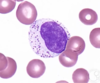

Which leukocyte is shown?

Monocyte